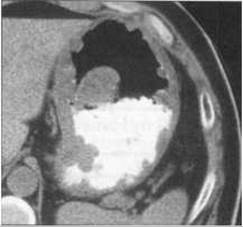

Мал. 176. Хронічний антральний гастрит на рентгенограмі з подвійним контрастуванням (А) та комп’ютерній томограмі з пероральним та внутрішньовенним контрастуваннм (Б). Потовщені складки слизової оболонки і стінка шлунка (стрілка).